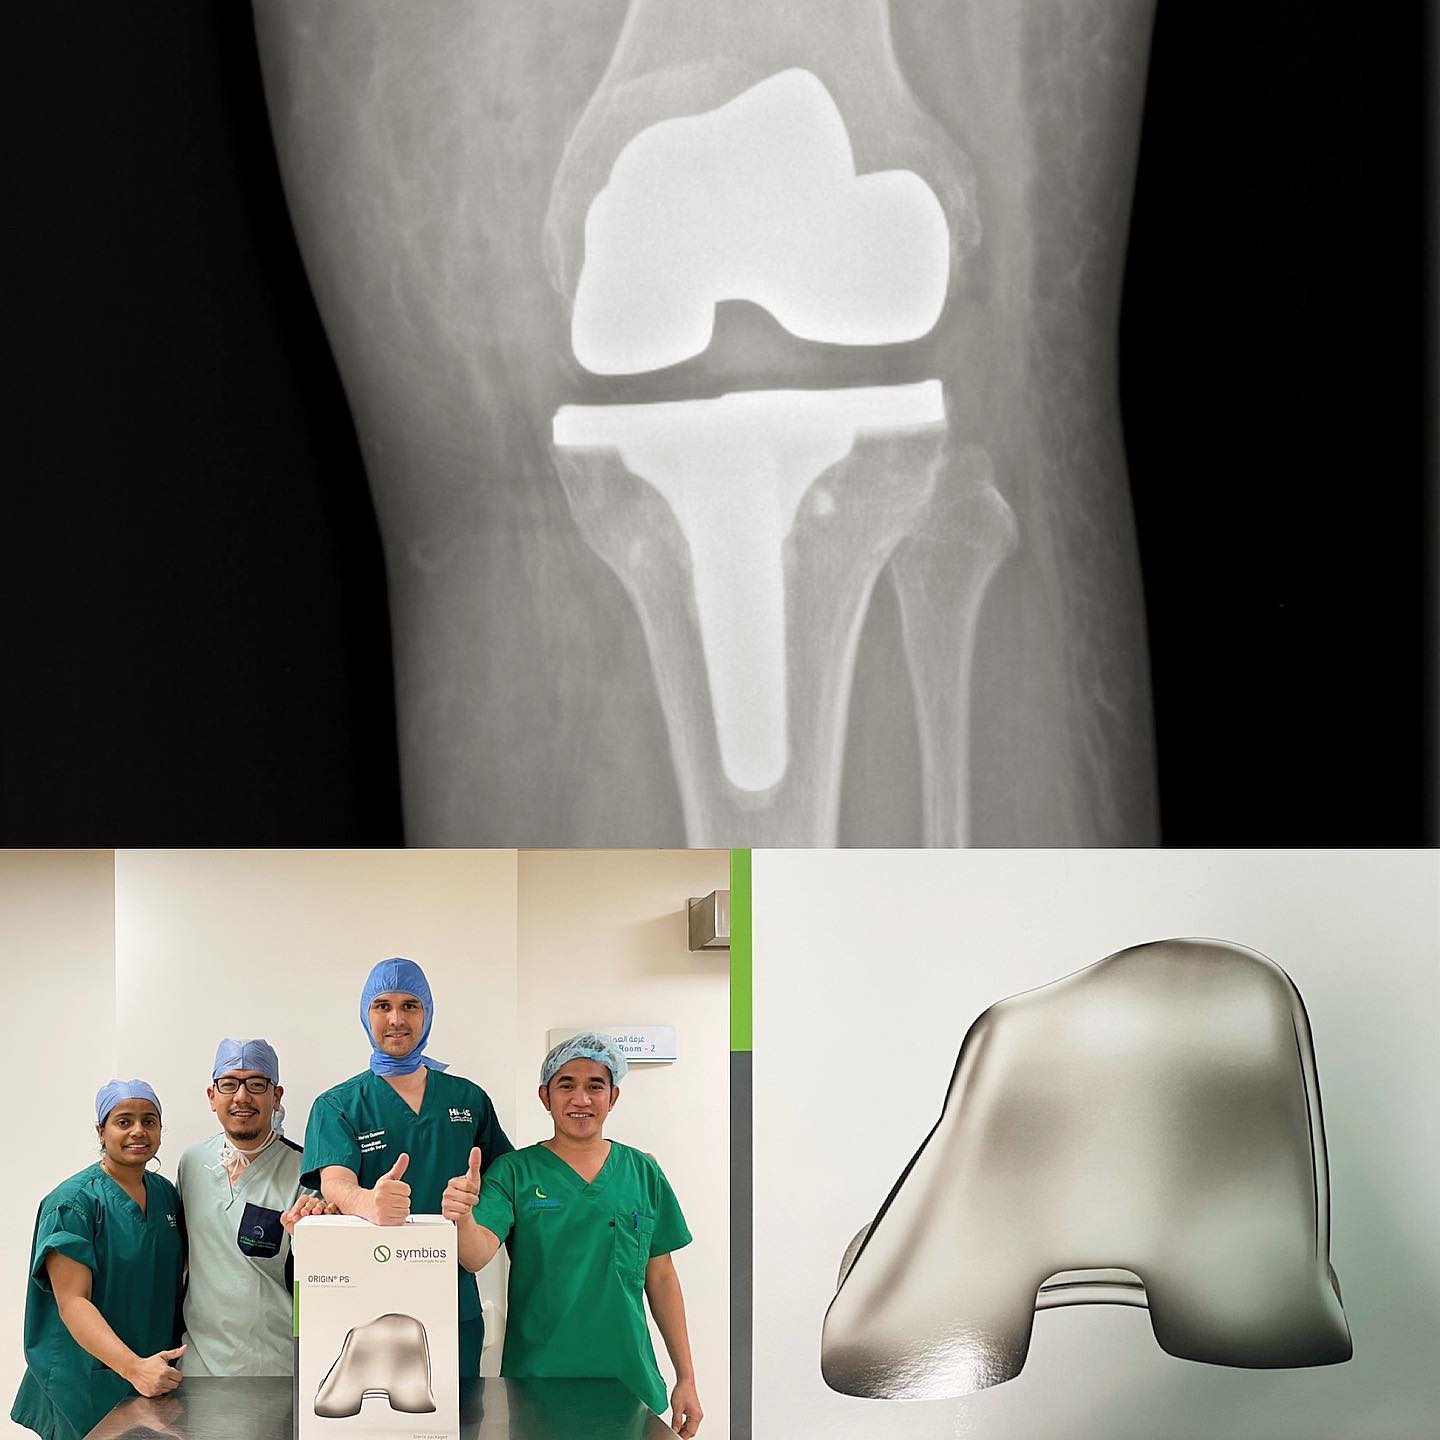

For cases requiring surgical intervention, Dr. Hervé Ouanezar and his dedicated team work closely to ensure a swift and successful recovery. Post-operative care is managed collaboratively with expert physiotherapists and, when needed, with the nation’s leading sports medicine physician.

Our approach incorporates modern surgical techniques, including arthroscopy, minimally invasive procedures, and personalised interventions tailored to each patient’s needs.